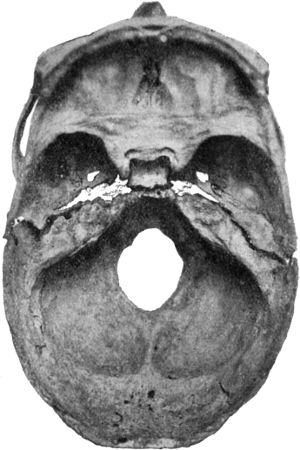

191.Transverse Fracture through Middle Fossa of Base of Skull368